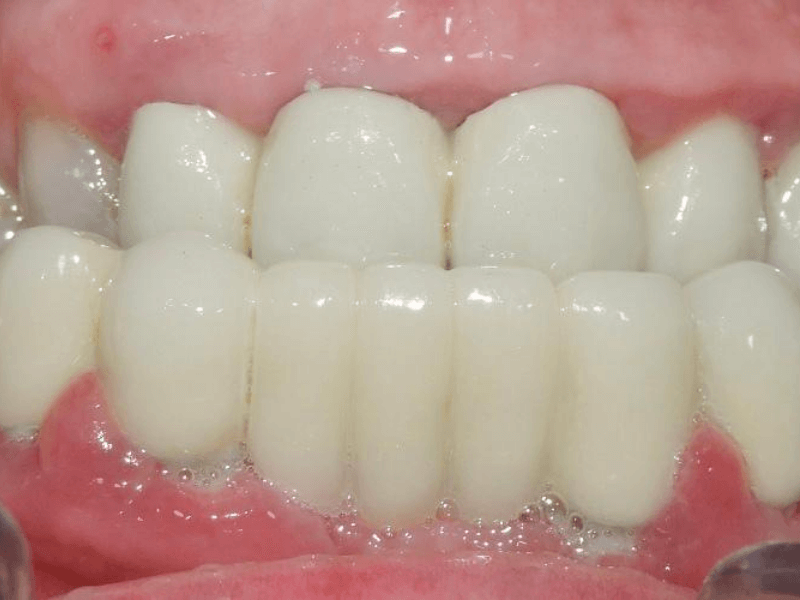

La recuperación es muy rápida, a los 7 días de la colocación de los implantes te revisamos el tratamiento y te retiramos los puntos de sutura. A partir de ese momento esperamos 3 meses, ya que es el tiempo estimado en el que se produce la osteointegración (unión del implante al hueso), y es en ese momento cuando ya podemos proceder a la sustitución de la prótesis inmediata por una definitiva. Mucho más estética y adaptada para masticar como si de dientes naturales se tratara. Tus nuevos dientes están dotados de una estructura interna de metal que les aporta resistencia. Su forma, color y tamaño son de apariencia natural.